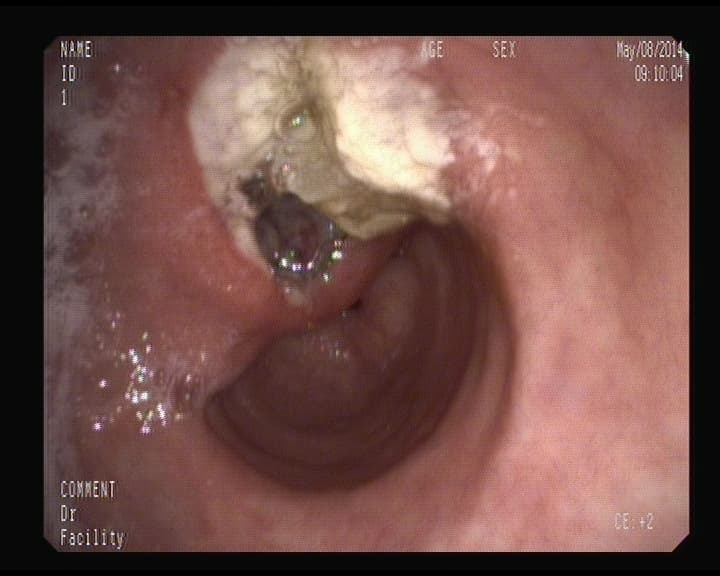

Cáncer Rectal.

Crecimiento infiltrante que afecta la mitad de la circunferencia en el extremo distal del intestino grueso- Recto-.